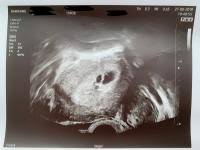

In dieser Fruchthöhle finden sich gelegentlich bereits kleine weißliche Flecken die durch die embryonalen Strukturen hervorgerufen werden. Woche SSW5 Alter 3 Wochen. In der Regel werden Zwillinge bereits bei der ersten Ultraschalluntersuchung entdeckt die etwa in der sechsten Schwangerschaftswoche erfolgt.

Sicherlich haben Sie jetzt das Bedürfnis all Ihren Freundinnen und Freunden vom kleinen Geheimnis zu erzählen das da in Ihrem Bauch wächst. Die vom Arzt korrigierte geschätzte SSW nach dem Ultraschall ist ca. Ab wann ist es möglich.